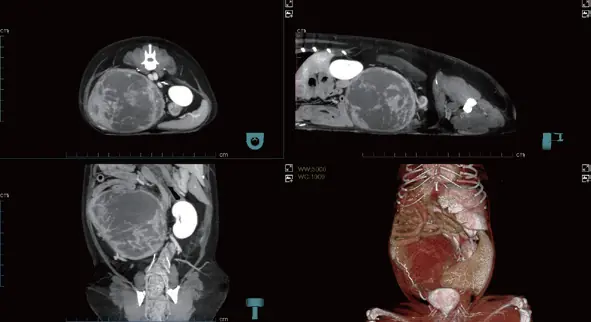

Simetrik prostat büyümesi ile birlikte homojen kontrastlanma. Halka şeklinde kontrastlanan çok sayıda kistik yapı. Büyümüş internal ve eksternal iliak lenf düğümleri.

Arteriyel, venöz ve geç fazları tek bir taramada otomatik olarak kaydeder. İş akışını kolaylaştırır ve fazlar arası karşılaştırmaya imkân tanıyarak lezyonların daha net ve verimli şekilde saptanmasını sağlar.